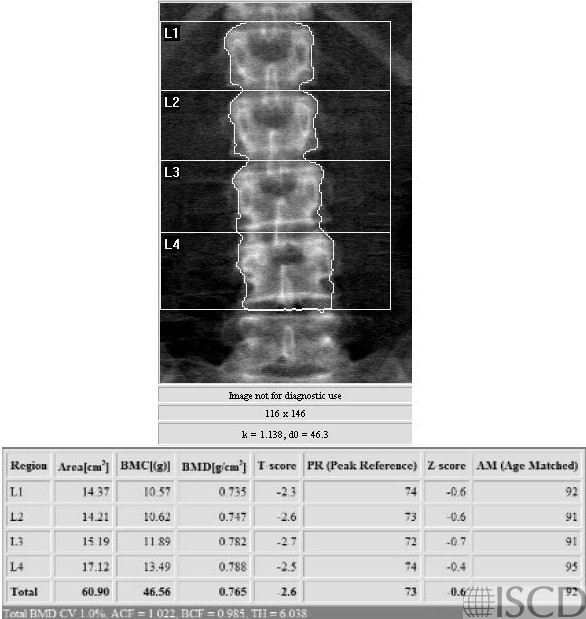

This is the lumbar spine Hologic DXA scan from a woman with biospy-proven celiac disease.

This is a DXA scan from a 65-year-old Caucasian female referred with low bone mineral density and a poorly healing fracture. The second cause work up demonstrated celiac sprue with anti-TTG > 150. The diagnosis was subsequently confirmed on a small bowel biopsy. There are no specific DXA finding that would suggest celiac sprue over another secondary cause. A thoughtful secondary cause work up is important in patients being evaluated for low bone mineral density and fracture. Relatively large increases in bone mineral density have been reported with the treatment of celiac sprue with a gluten-free diet.